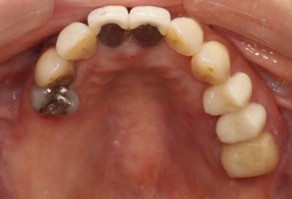

20代 男性

治療後

治療後- リスク・副作用

(薬・注射・レントゲン・CT・データ分析・骨造成・サージカルステント・血液検査・仮歯) - 年齢/性別

- 20代/男性

- 患者の具体的な症状

- 1年前に左上12 右上1の根の治療をし、その後放置していたら、左上2が破折した。

左上2インプラント補綴 左上1右上1オールセラミック装着。

歯根破折と虫歯による痛み、審美障害を主訴として来院。 - 検査方法

- コーンビームCT、レントゲン撮影

- 診断結果

- 左上2 歯根破折

- 治療詳細

- 左上抜歯後、インプラント埋入1本

骨造成あり 局所麻酔

インプラント治療後、左上1右上1セラミック修復2本 - 通院回数

- 9回

- 治療期間

- 12か月